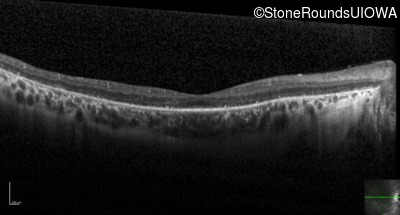

Optical Coherence Tomography - Left - 20/50 -1 sc

Exemplar / OCT Stack

OCT Stack